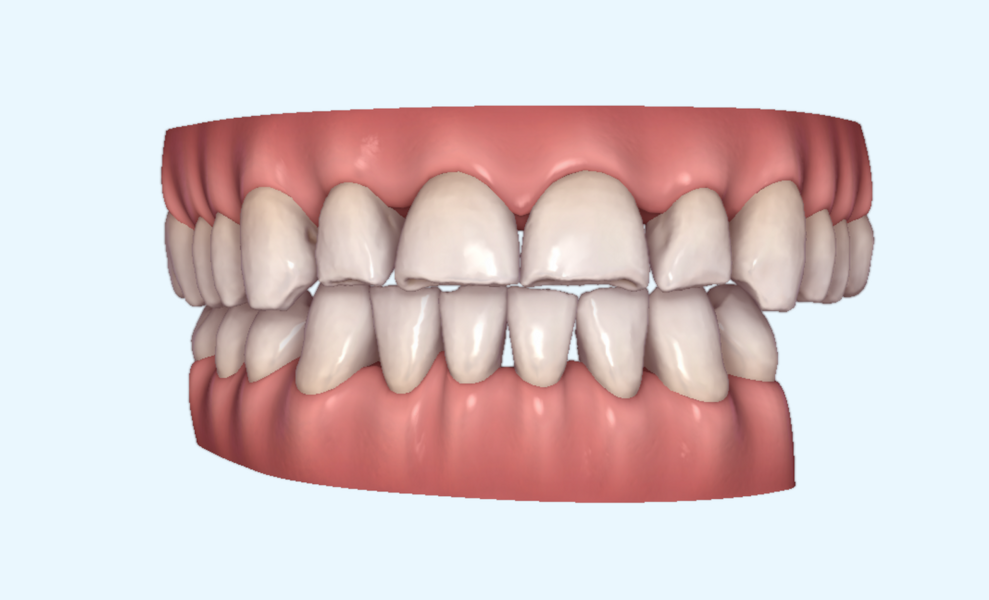

This patient, like all patients requiring interdisciplinary rehabilitation, had to first undergo periodontal treatment and caries restoration (Fig. 17). At the same time, it was important to rehabilitate swallowing with Froggymouth and relax the masticatory muscles and relieve the TMJs with an occlusal device. We could then study the orthodontic treatment plan using Invisalign ClinCheck (Align Technology) and showed the treatment plan to the interdisciplinary team and to the patient (Fig. 18). We were then able to create the correct sequence of orthodontic treatment, bone augmentation and implant surgery needed for the posterior edentulous spaces.

After the first phase of aligner treatment, we had achieved better inter-arch coherence, better maxillary arch expansion, and some space for improving the anterior tooth proportions restoratively (Fig. 19). We then temporarily restored the anterior teeth directly with composite, closing the spaces, improving the tooth proportions and further increasing the maxillary arch expansion (Fig. 20). We used restorative arch expansion to reduce the orthodontic destabilisation of the teeth to achieve the correct inter-arch coherence and retain the teeth in the cortical bone.38 A refinement aligner phase was undertaken to improve the final alignment of the gingival zenith and to improve the inter-arch coherence (Fig. 21). The periods of the first orthodontic phase and of the refinement were used to augment the mandibular and maxillary bone and to place the implants (Fig. 22). At the end of the orthodontic treatment, the case was finalised with ceramic veneers in the anterior area and temporary restorations on the implants in the posterior area (Figs. 23–26).